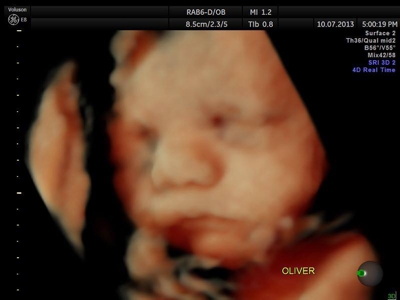

Fotografías de ecografías 4D HD/5D

Haga click sobre las imágenes para ampliar